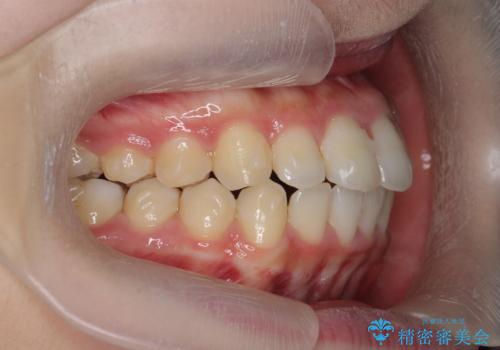

出っ歯を治すマウスピース矯正

- 出っ歯のように見える前歯の角度を治したい、と矯正治療を希望され来院されました。

抜歯をせずにマウスピース矯正システムインビザラインを用いてしっかりと前歯の角度を改善していきます。

前歯の角度だけでなく内側に倒れ込んでいた奥歯もしっかり起こすことで咬合関係も理想的に仕上げています。